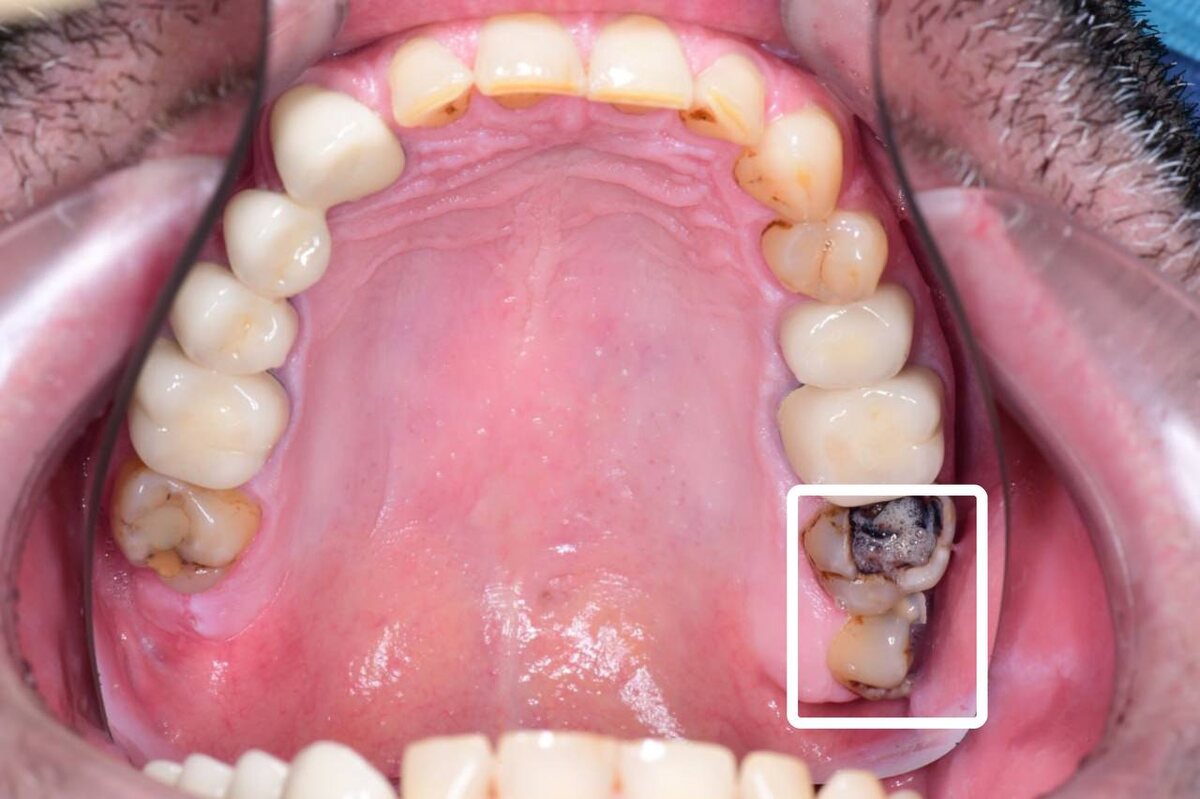

Разрушены зубы 2.7 и 2.8.

А вот зуб 1.7 требовал лечения. На зубе сразу две старые пломбы, первая — совсем старая, ещё из химического композита, вторая пломба — из светового композита, но тоже изношенная. Кроме этого, на границе с зубом 1.6 нашлось потемнение тканей — всё указывало на скрытый кариес.

Зуб 1.7 требовал лечения